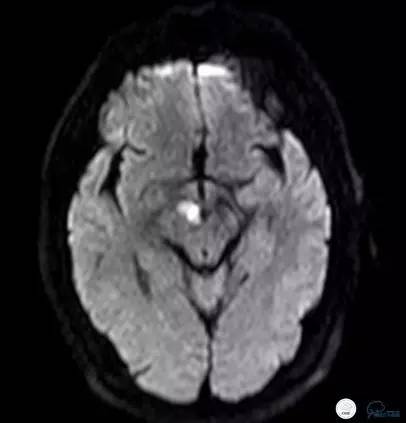

就诊于外院查头颅核磁DWI+MRA(图1-2):中脑右侧及右侧丘脑新鲜脑梗死,椎基底动脉及双侧大脑后动脉未见显影。住院予波立维、拜阿司匹林抗血小板聚集、立普妥降脂治疗后症状无好转,病情逐渐加重。为进一步行血管内治疗来我院。

图1